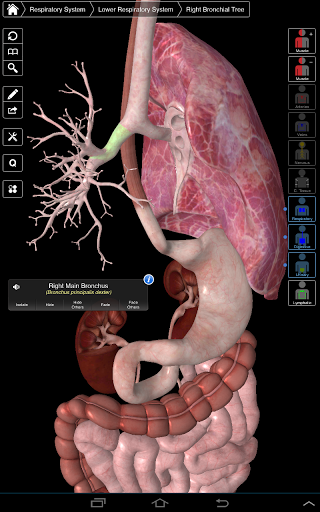

Essential Anatomy 3 representa lo último en tecnología 3D innovadora y diseño innovador. Un motor de gráficos 3D de vanguardia, creado a medida por 3D4Medical desde cero, alimenta un modelo anatómico altamente detallado y ofrece gráficos de calidad excepcional que ningún otro competidor puede lograr.

La aplicación representa un enfoque único para el aprendizaje de la anatomía general. Los gráficos no tienen paralelo y hacen que el aprendizaje, a través del uso de contenido informativo y características innovadoras, sea una experiencia rica e interesante.

⁃Respiratorio

NUEVA TECNOLOGÍA 3D

Essential Anatomy 3 es receptivo, visualmente impactante y sin esfuerzo. La aplicación es totalmente en 3D, lo que significa que puedes ver cualquier estructura anatómica de forma aislada y desde cualquier ángulo.

---- Más de 4,000 estructuras anatómicas altamente detalladas